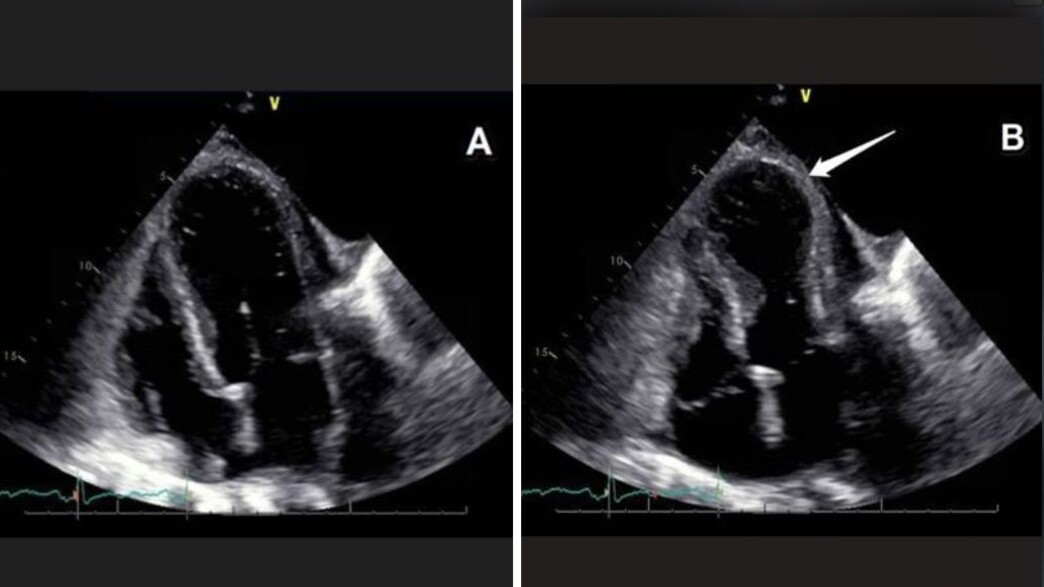

באקו לב ניתן לראות ממצא אופייני: הפרעה בהתכווצות שריר הלב, לרוב באזור חוד הלב, שמקבל צורה של התרחבות - תופעה המכונה Ballooning )כשהבסיס מתכווץ והחוד נשאר רפוי מתקבל מראה של בלון). "זה מראה דרמטי", היא אומרת, "אבל בניגוד להתקף לב אמיתי, כאן אין חסימה בעורקים".